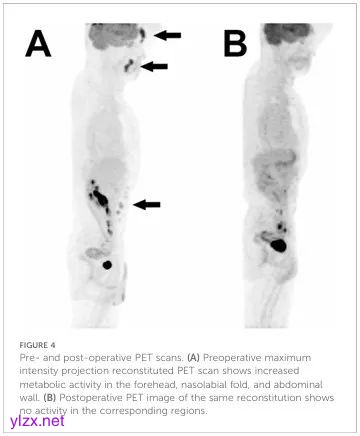

在确诊为组织细胞肉瘤后,随后切除了前额、鼻唇沟和腹部的所有剩余病变(图3A-C)。由于切除的完全性,没有进行辅助放化疗。患者正在接受无病随访,对结节的异常形成进行彻底的体检,并每6个月进行一次PET-CT扫描(图4)。

图4:术前和术后PET扫描。(A) 术前最大强度投影重建PET扫描显示前额、鼻唇沟和腹壁的代谢活动增加。(B) 相同重建的术后PET图像显示相应区域没有活动。